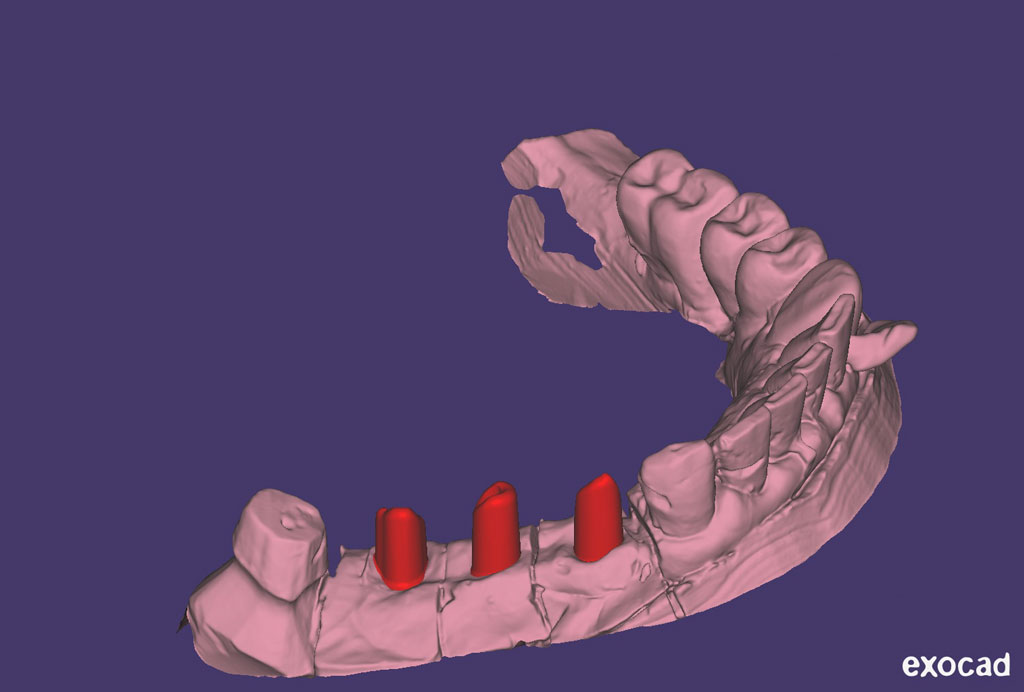

Fehlen in der Front oder im Seitenzahnbereich mehrere Zähne, ist eine Brücke oder Prothese vollkommen unnötig. Die fehlenden Zähne können entweder einzeln durch eine entsprechende Anzahl von Implantaten oder durch implantatgetragene festsitzende Brücken ersetzt werden. Das Bild der Kronen zeigt die drei Verschraubungen deutlich, im Mund liegen diese verdeckt am Gaumen oder im Bereich der Zunge.

DVT mit 3D-Planung